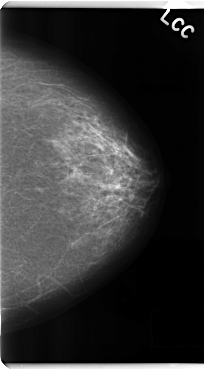

ics_version 1.0 filename C-0182-1 DATE_OF_STUDY 13 5 1996 PATIENT_AGE 62 FILM FILM_TYPE REGULAR DENSITY 1 DATE_DIGITIZED 19 3 1998 DIGITIZER LUMISYS LASER SEQUENCE LEFT_CC LINES 4792 PIXELS_PER_LINE 2648 BITS_PER_PIXEL 12 RESOLUTION 50 NON_OVERLAY LEFT_MLO LINES 4752 PIXELS_PER_LINE 2512 BITS_PER_PIXEL 12 RESOLUTION 50 NON_OVERLAY RIGHT_CC LINES 4752 PIXELS_PER_LINE 2728 BITS_PER_PIXEL 12 RESOLUTION 50 OVERLAY RIGHT_MLO LINES 4728 PIXELS_PER_LINE 2696 BITS_PER_PIXEL 12 RESOLUTION 50 OVERLAY |